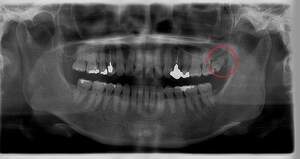

右下奥歯が痛い症例

- 抜歯前写真(レントゲン)

| 親知らずの生え方 | 斜めに生えている |

| 抜歯内容 | レントゲン上で右下の親知らずが大きく虫歯になっており、斜めに生えていることもあり患者様の希望により抜歯することとなりました。 当日は痛みがあったため抗生剤と鎮痛剤にて炎症を抑え、後日歯ぐきを切開し、抜歯を行いました。 レントゲン上でも分かるように親知らずの根が二つに分かれており根が折れてしまう可能性がありましたが、このケースでは事前にCTを撮影し、歯の位置、根の方向を確認していたため根が折れることなく抜歯ができました。 術後数日は腫れと痛みがありましたが、薬の服用で抑えることができ、1週間後の糸取りの際には痛み、腫れともになくなっていました。 |